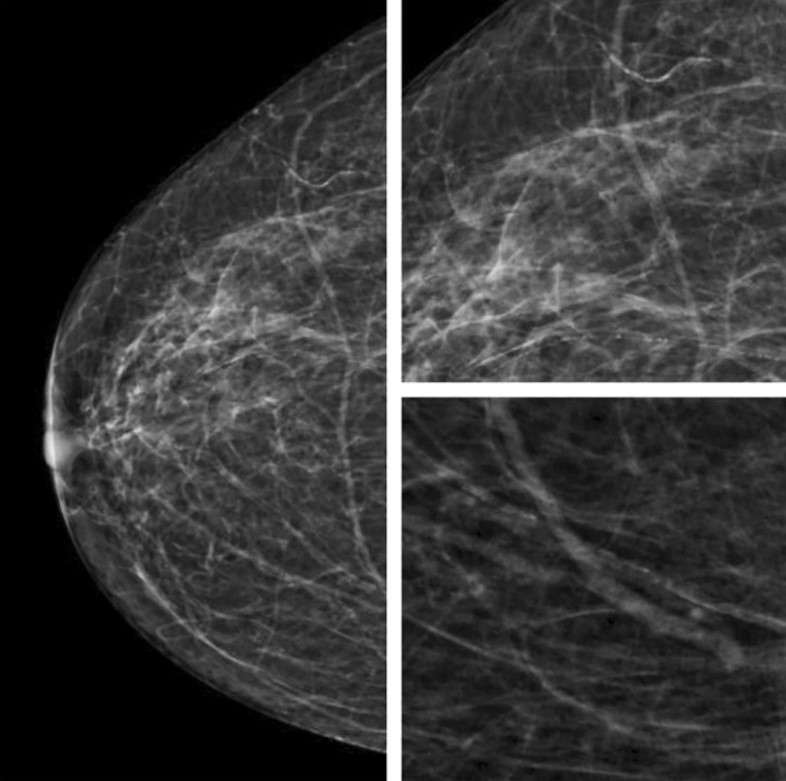

Внутрикожные кальцинаты локализованы преимущественно в дерме и являются результатом обызвествления протоков сальных желез. Чаще всего локализуются группами, имеют кольцевидную или точечную форму (Рис.3).

Для фиброзно-кистозных изменений характерны кальцинаты по типу Weddell. Как правило, они имеют квадратную, треугольную или трапецивидную форму (Рис.4).